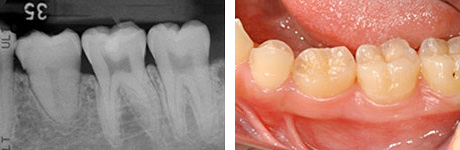

移植後4ヶ月。

移植歯はコンポジットレジンで修復が行われています。